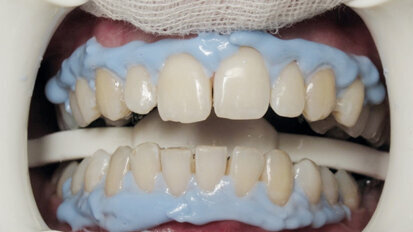

Bělení zubů a ortodoncie

St. 9. září 2020